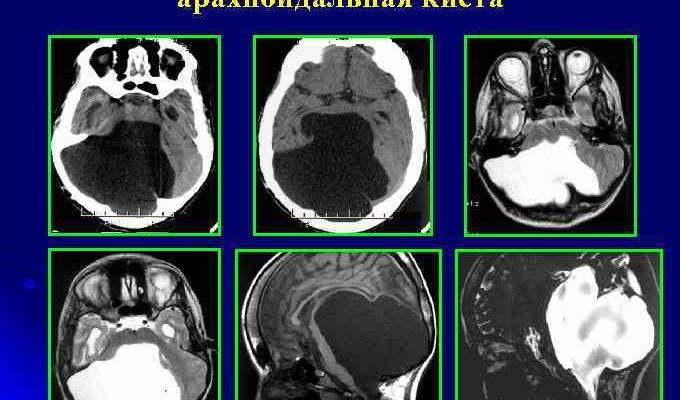

Основным методом диагностики арахноидальных кист головного мозга является проведение магнитно-резонансной томографии (МРТ). Чтобы определить местонахождение опухоли, пациенту вводят специальные контрастные вещества, которые накапливаются в кисте, чтобы ее можно было обнаружить. МРТ обычно используется для диагностики арахноидальной кисты.

МРТ также можно использовать, чтобы отличить кисты от кровоизлияний, гематом, гемангиом, абсцессов и других заболеваний с похожими симптомами. Более того, МРТ позволяет обнаружить кисту, даже если у пациента еще нет симптомов, а киста имеет размер всего несколько миллиметров.